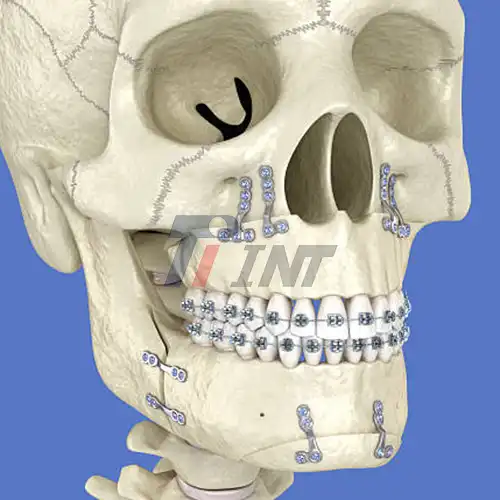

2025-12-17 08:34:05Minimizing Complications in Mandibular Fracture Repair with Titanium Plate Fixation

2025-12-18 08:33:05Post-Surgery Recovery with Titanium Plate Fixation for Mandibular Fractures

2025-06-18 10:40:11Titanium Plates for Facial Fractures: A Trusted Solution for Orthopedic Surgeons